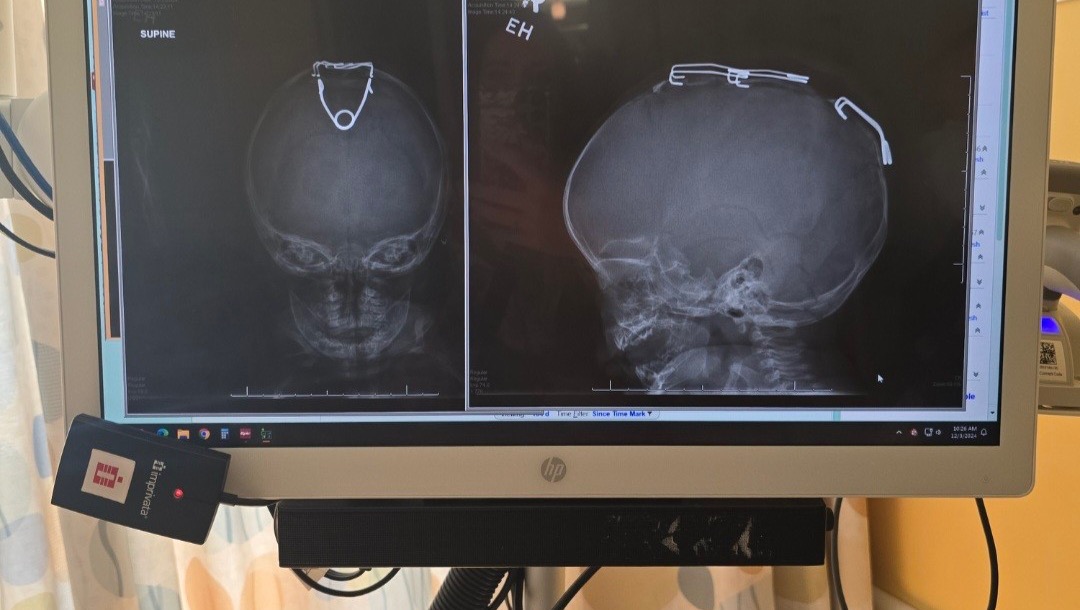

Wyatt was born with Scaphocephaly, a form of craniosynostosis that caused two of his skull plates to be fused prematurely, something that believe it or not, isn’t supposed to happen until 25! This caused his head to be misshaped and look more like a football than a basketball. (Sorry I don’t know how else to explain it, and I like sports lol). Wyatt had a strip crainiectomy with sagital springs placed in his skull to open it correctly and allow his brain to develop correctly (this was not just for a nice round head). Upon discussion with the doctors Amelia was told that it’s a fairly simple procedure and the doctor only knew of one instance of where there was complications due to spring malfunction. Well, Murphy’s Law took over from there, and sweet baby Wyatt now owns the title of the second malfunction.

Upon completion of the first skull surgery Wyatt had a bump on the top of his head and swelling on one side of his head. Amelia called and messaged the doctor daily, they reassured her to watch it and keep them posted. With frequent daily communication, she informed them it was raising unevenly, significantly higher on his right side. About a week post op a straw-like formation developed going from the bump on top of his head to his upper ear. It turns out, this was his skull.

Upon this development, Children’s became concerned and advised she immediately bring him in for imaging and evaluation. One of the springs was essentially prying his skull apart, lifting it off the side of his head. 8 days after having his skull broken and springs placed, he was readmitted for a second surgery.